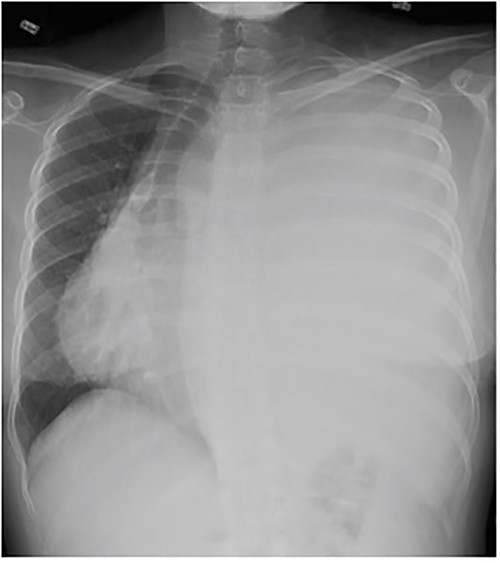

A 33-year-old woman presented to the emergency department following a motor vehicle accident. Imaging showed a large heterogenous intermediate density mass filling and expanding the left hemithorax, causing a complete collapse of the left lung and substantial right deviation of heart and mediastinum (Fig. 1). The patient complained of mild exertional dyspnea that had worsen over the past 6 months. Physical exam was unremarkable aside from decreased breath sounds on left side. Percutaneous core needle biopsy revealed spindle cells along with immunostatins consistent with SFT. Upon later questioning, the patient noted progressive anorexia with a 15 lb weight loss over the last 4 months and occasional dyspnea.

Frontal chest radiograph shows complete opacification of left hemithorax with significant mass effect.